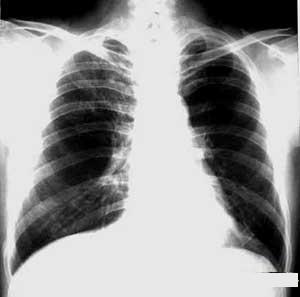

肺真菌病的X片圖後支氣管殘端的盲端內,近年報導增多,可能與廣泛套用廣譜抗生素、檢查切除標本較細緻有關。菌球系菌絲形成的圓形團塊病變局限發展緩慢,可存在數年。症狀有咳嗽咯血、胸痛、低熱等但多與原發病不易區別。咯血量可能很大而少量的咯血可能長期持續存在甚至使病人一直臥床不敢活動。咯血原因不明,有人認為有真菌感染的囊腔內壁肉芽有豐富的血管,菌球又是活動的,摩擦易致出血真菌球的X線檢查有特徵,囊腔內能見到半月形透亮區,隨體位而改變,一直保持在攝片時體位的最高處。

肺真菌病肺部X線改變有以下幾種:①肺炎型:病灶發展快,呈現大片緻密陰影。②支氣管肺炎型:治支氣管分布的小片陰影或肺紋理明顯增加,慢性病例有纖維化及肺氣腫。③肺膿腫型:由肺炎型演變或合併感染成膿腫,內可有透亮區或液平面。④炎症腫塊型:炎症腫塊有纖維包膜包圍密度均勻,病程慢。⑤混合型:曲菌球由曲菌絲和纖維黏液混合構成寄生在肺內囊性病變中,如結核、囊性支擴等,菌球與囊腔間有氣體存在,呈現一彎形空隙,有時還能隨體位而轉動,立位、平臥及側臥位片上均可見到上方存在的空氣影,這類患者常有咯血是惟一X線改變有明顯特點的真菌病。⑥胸膜炎型:胸膜肥厚或有胸腔積液。